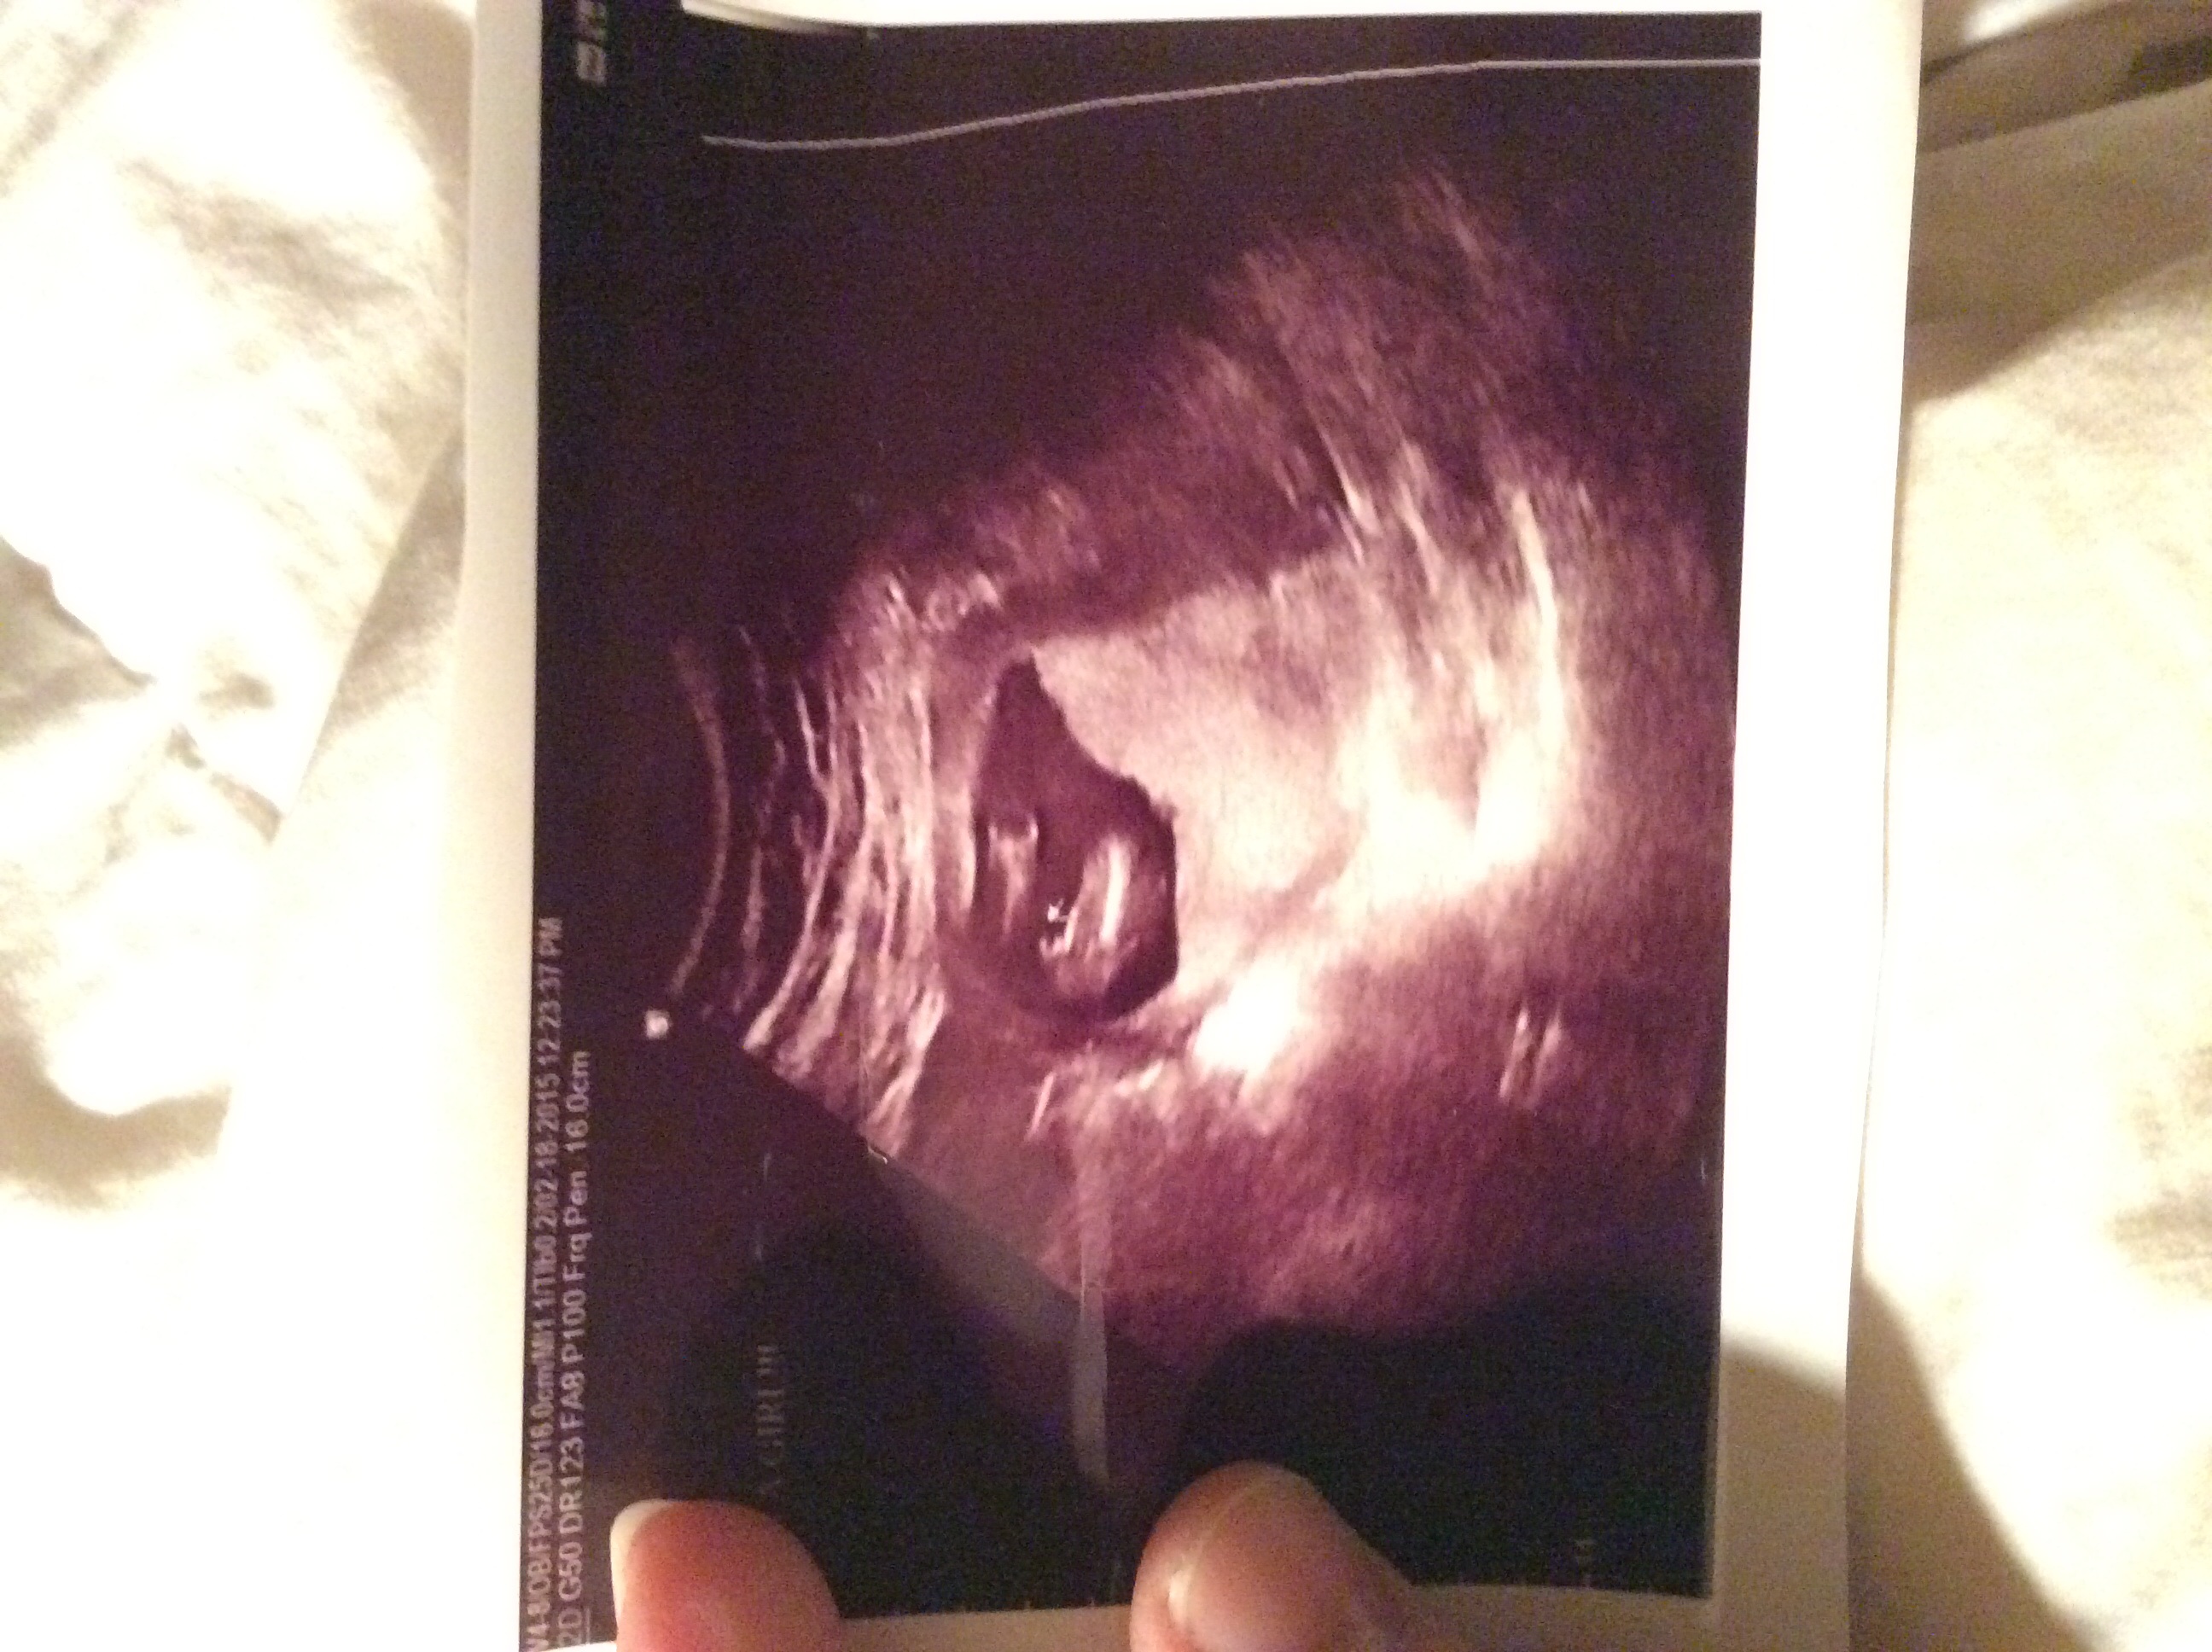

I had an elective gender scan yesterday and the tech said 100% girl, I've always heard you see 3lines with a girl but this ultrasound looks like a V. With my son I could clearly tell at my 16 week elective that he was a boy, it was sticking straight out. I just hear so many stories of girls ending up being boys. I'm gonna ask my dr what he thinks but can y'all give me opinions on the pic and tell me if you think it's a girl? Thanks! image

• I've heard more of the tech telling you it's a boy and having it be a girl than the other way around since their genitals can be swollen. That being said if the tech said girl id go with girl and just confirm at your A/S. Plus, looks like what my ultrasound did and I'm having a girl. :)